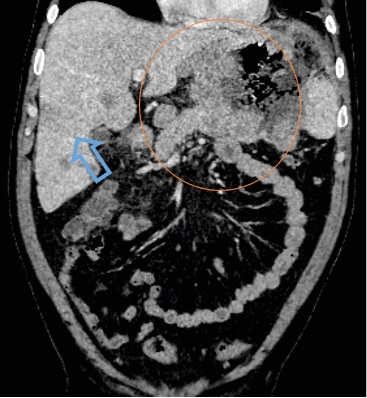

The paper examines and analyzes data obtained by radiological research methods in 15 HIV-infected patients with a histologically verified plasmoblastic lymphoma (PBL) who were treated in the period from 2014 to 2023 in the hematology department of the Surgut District Clinical Hospital. We obtained data that do not contradict the reviews of other researchers. Plasmoblastic lymphoma develops in people aged 40–50 years, malignant lymphoma is commonly first diagnosed at stage III or IV according to the Ann Arbor stages. It is characterized by damage to the oral cavity, but cases of damage to the gastrointestinal tract are not uncommon. This type of lymphoma occurs in 83% of cases in people with severe immunosuppression. In 100% of cases, the association of lymphoma with Epstein–Barr virus (EBV) is revealed.